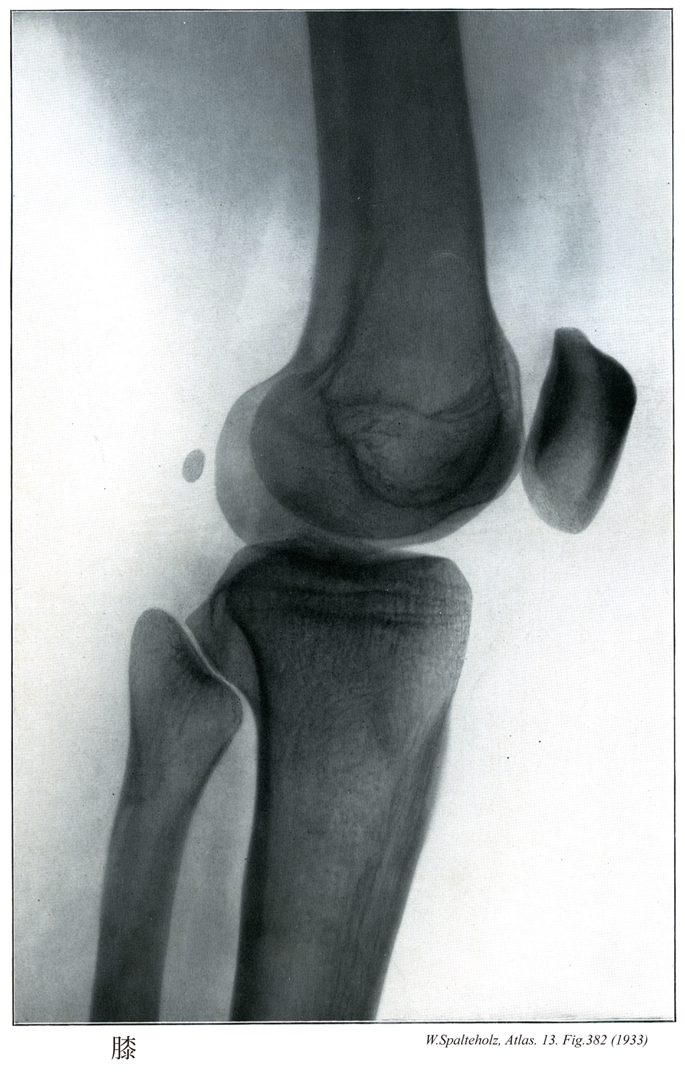

382

【Knee

膝;ヒザ

Genu】

→(大腿と下腿の間の関節部。)